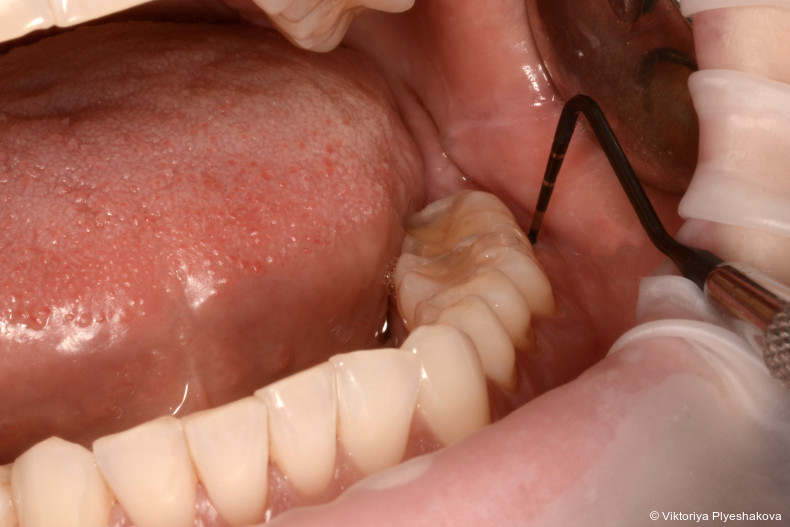

Vor der Instrumentierung wird ein Reinigungsgel aus Aminosäure-gepuffertem Natriumhypochlorit in die Tasche eingebracht. Dieses bewirkt eine deutliche Reduktion der Bakterienpopulation und erleichtert sowohl die Entfernung von Biofilm als auch von infiziertem Granulationsgewebe. Nach der Instrumentierung wird vernetzte Hyaluronsäure eingebracht, um die Gewebereparatur zu fördern, die Heilung zu beschleunigen und so einen Schutz vor erneuter bakterieller Invasion der behandelten Stelle zu verhindern.

Um das Instrumentierungsprotokoll zu verbessern und chi­rurgische Eingriffe zu vermeiden, verwenden wir vor und während der Instrumentierung ein Aminosäure-gepuffertes Na­triumhypochloritgel (Perisolv, Regedent GmbH). Es weicht das entzündliche Granulationsgewebe und die extrazelluläre Matrix des Biofilms auf, wirkt antimikrobiell und verbessert so die Effizienz des Debridements.4 Nach erfolgter Instrumentierung wird vernetztes Hyaluronsäuregel (xHyA – hyaDENT BG, Regedent GmbH) in die Tasche eingebracht. xHyA fördert bekanntermaßen die parodontale Heilung, reduziert Entzündungen und versiegelt so die Stelle gegen erneute Kon­ta­mination.5 Diese Behandlungssequenz wird als Clean & Seal-­Konzept bezeichnet.

Der Behandlungsplan wurde in drei Phasen durchgeführt. In den Pha­­sen I und II wurden die Anweisungen zur Mundhygiene verstärkt, um die Plaquekontrolle zu verbessern, gefolgt von einem supra- und subgingivalen Debridement mit Ultraschall (mectron GmbH) und Hand­instru­menten (Gracey-Küretten). Das Hypochlorit-Reinigungsgel (Perisolv) wurde adjuvant vor und während der Instrumentierung appliziert. Nach erfolgter Instrumentierung wurde vernetzte Hyaluronsäure (hyaDent BG) in die Taschen eingebracht, um die Wunde zu stabilisieren und die Regeneration zu fördern. Nach sieben Tagen wurde eine erneute Applika­tion der vernetzten Hyaluronsäure vorgenommen, um den natürlichen Abbau zu kompensieren, eine sekundäre bakterielle Rekolonisation zu verhindern und einen verlängerten regenerativen Effekt zu erzielen. Die Phase III (Erhaltungsphase) umfasste eine unterstützende Parodontitistherapie alle drei Monate mit Verbesserung der Mund­hygiene und stetiger Überwachung der Sondierungstiefe und des Sondierungsblutens.

Bei der Nachuntersuchung nach drei Monaten war ein deutlicher Rückgang der Entzündung und der Sondierungsblutung zu verzeichnen. Die Sondierungstiefen wurden auf 3 bis 5 mm reduziert. Nach sechs Monaten wiesen alle behan­delten Stellen (17, 16, 36-37, 46-47) stabile Sondierungstiefen von ≤ 4 mm auf, ohne Zeichen von Sondierungsblutung oder Beweglichkeit. Die Röntgenkontrolle zeigte erste Anzeichen einer Knochenauffüllung in den zuvor betroffenen Bereichen. Die Patientin berichtete von verbessertem Wohlbefinden und Zufriedenheit.